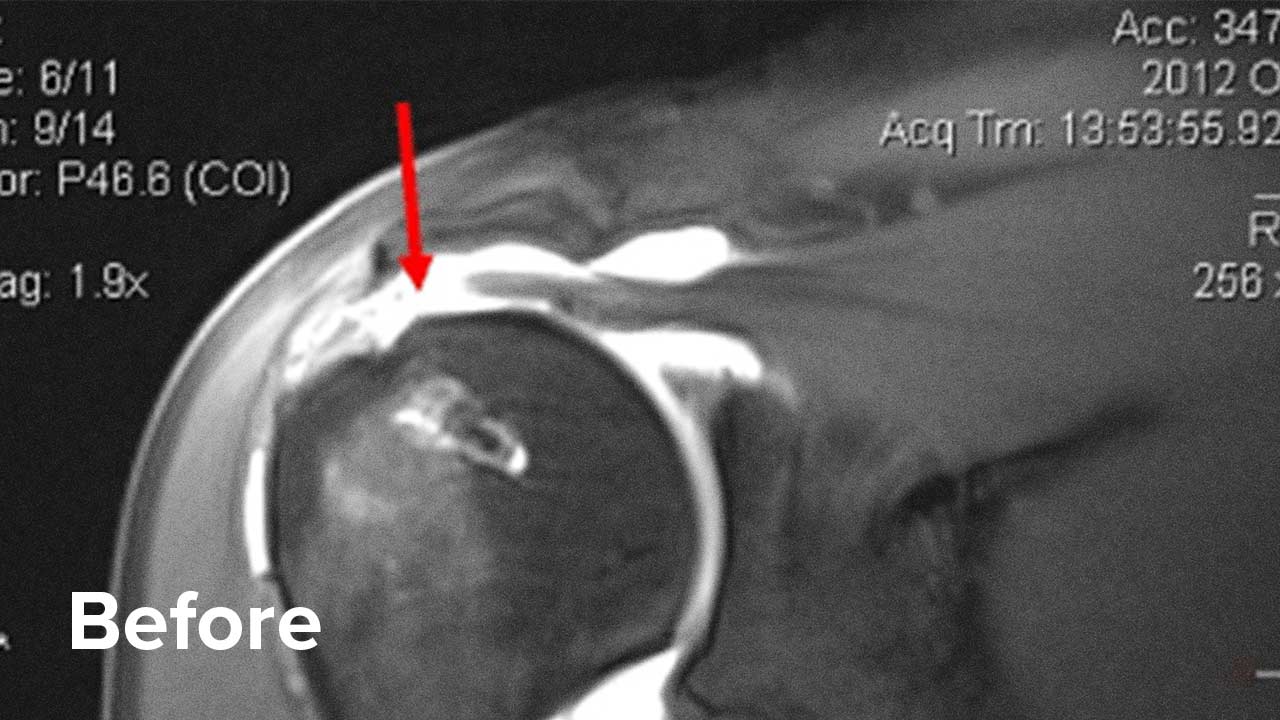

Before and After Shoulder Repair MRI Images

Take a look at the outcomes of two of our patients who chose to have a Regenexx procedure instead of surgery.

Scroll the arrow to the right to see the MRI of the rotator cuff before the treatment and to the left to see the outcome. The BEFORE shows a torn rotator cuff. The arrow points at a gap where the tendon should be. Once treated, the area will look like a dark band going diagonally, as seen on the AFTER.

Patient 2 MRI